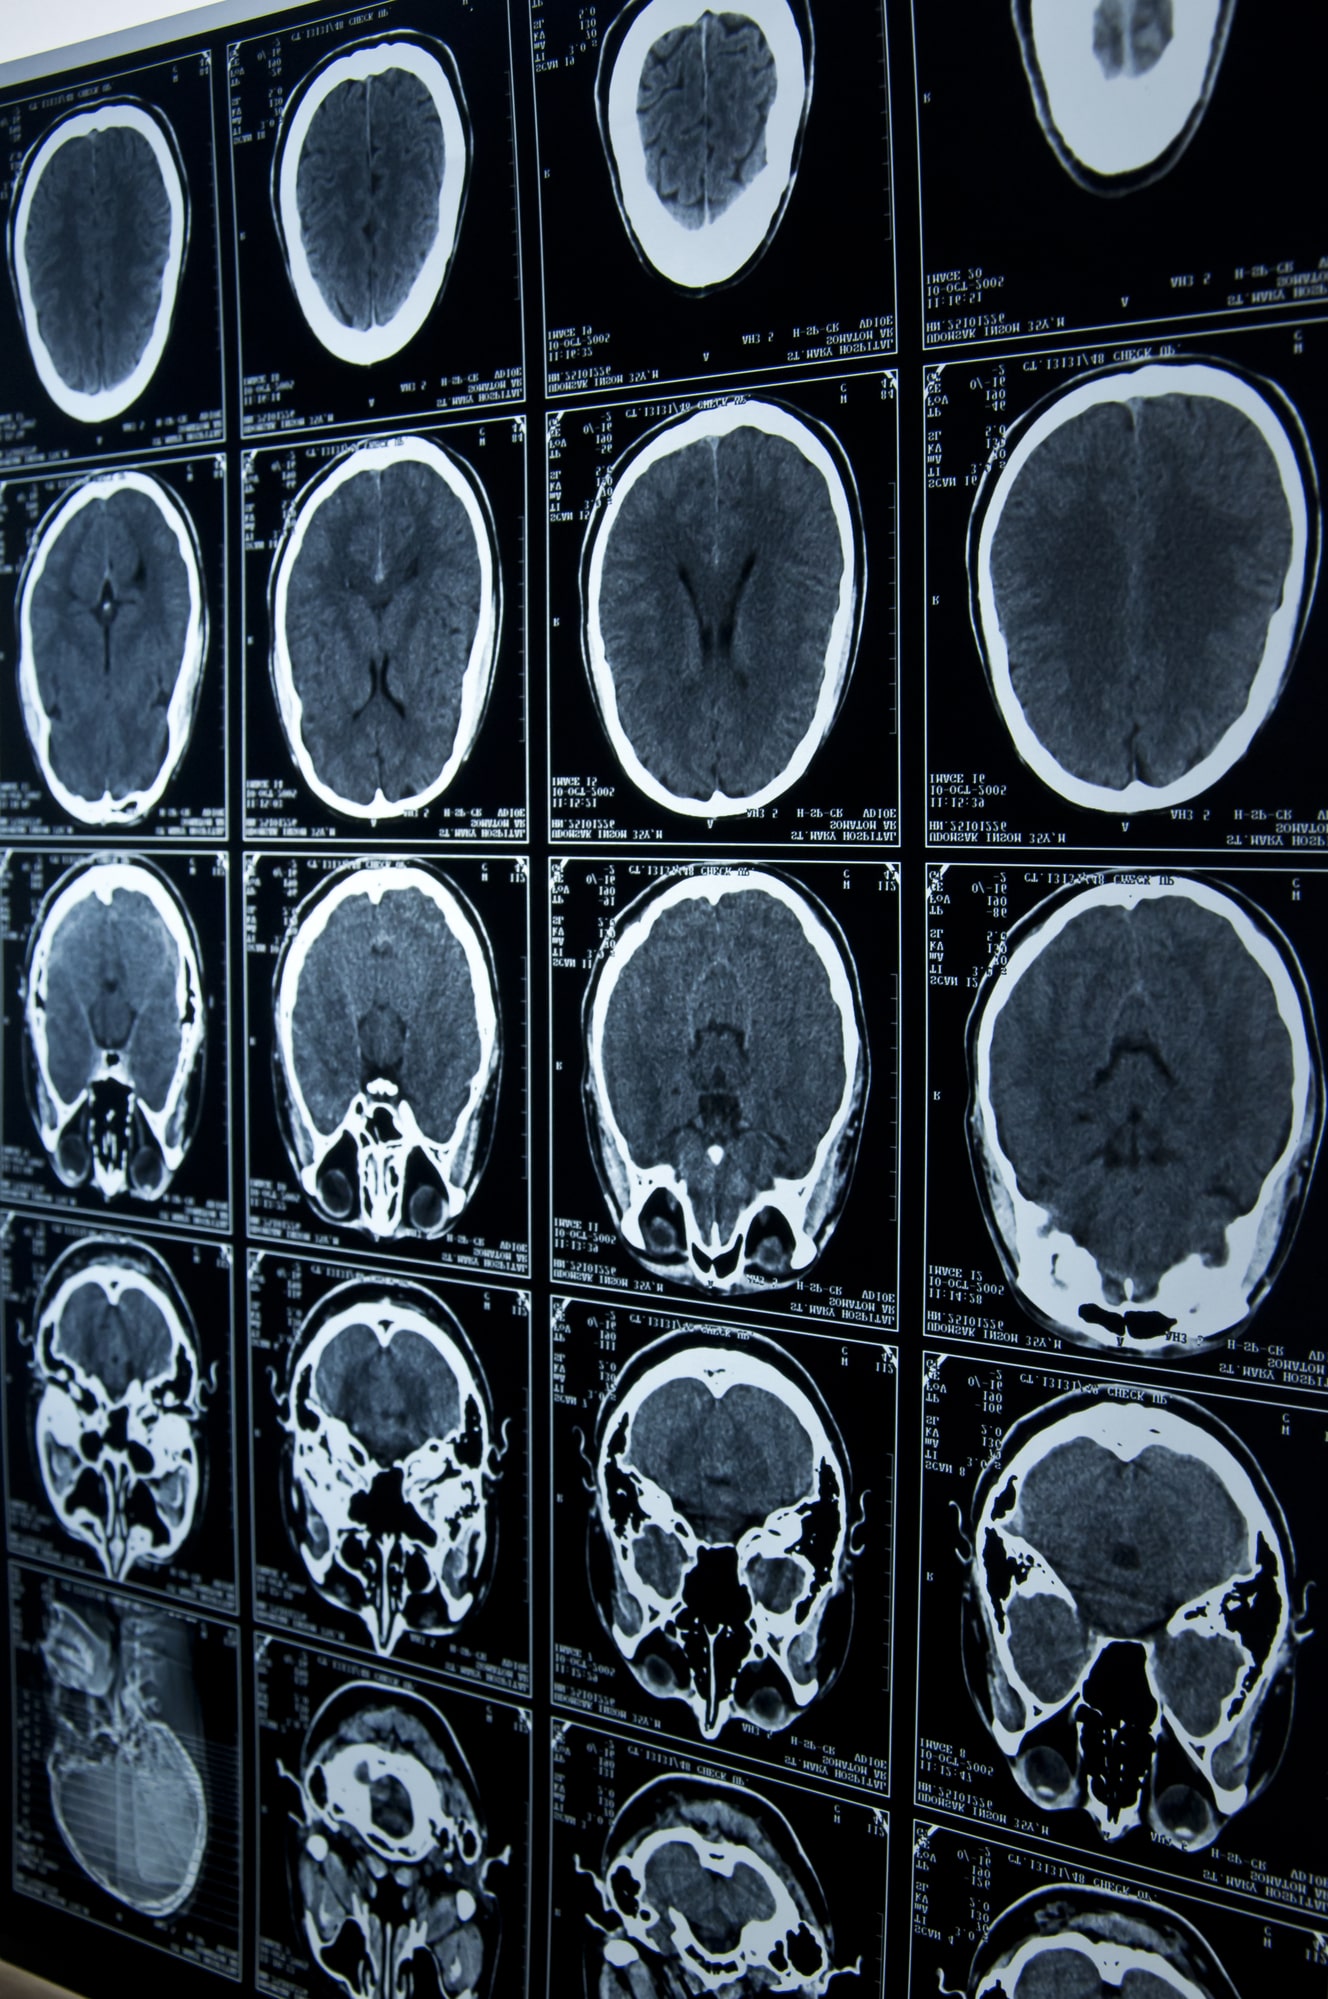

Brain injuries are among the most detailed and life-altering cases we handle. From concussions to severe trauma, the effects can include memory loss, cognitive decline, mood changes, and permanent disability. When someone’s negligence causes such harm, our head trauma lawyers step in to demand accountability.

Our concussion lawyers understand how overwhelming this process can feel. Our team works quickly to investigate what happened, gathering medical records, witness accounts, and professional opinions to establish the cause and impact of the injury. Whether your brain injury resulted from a car crash, fall, workplace accident, or sports-related impact, we build the evidence needed to show how the event has affected every area of your life.

As experienced Fishers brain injury attorneys, we know that recovery doesn’t stop once the initial medical treatment ends. Many victims require long-term rehabilitation, speech therapy, occupational therapy, and ongoing psychological care. We collaborate with life-care planners and neurologists to fully document your current and future needs, ensuring your claim reflects the lifelong costs of your injury.